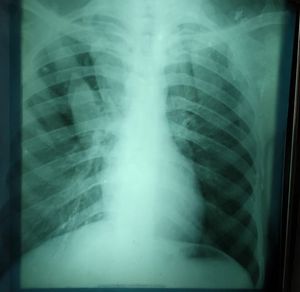

Rediology quiz

What is your diagnosis

Chronic

Pneumonia

Acute

Pneumothorax

Bronchitis